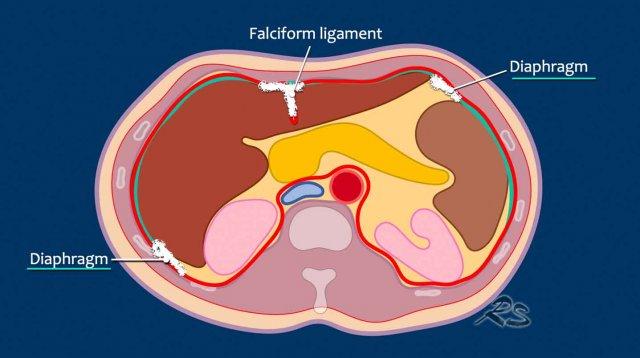

Phúc mạc gồm hai lớp.

Phúc mạc thành là lớp ngoài, bám vào thành bụng trước và sau (màu đỏ).

Phúc mạc tạng là lớp trong, bao phủ các tạng trong ổ bụng (màu xanh).

Mạc treo ruột có cấu trúc gồm hai lớp phúc mạc.

Mạc nối lớn là một nếp gấp lớn gồm bốn lớp phúc mạc tạng.

Nó trải dài thành hai lớp từ bờ cong lớn của dạ dày, đi xuống phía trước ruột non rồi gấp ngược lại để đi lên đến kết tràng ngang.

Mạc nối lớn bao gồm dây chằng vị-đại tràng, nối dạ dày với kết tràng ngang, và dây chằng vị-lách, nối dạ dày với lách.

Một số vùng giải phẫu đặc biệt có xu hướng là đích đến của các tế bào ung thư di căn phúc mạc.

Nguyên nhân là do dòng chảy theo chiều kim đồng hồ của dịch trong ổ bụng về mặt sinh lý, xuất phát từ sự thay đổi áp lực trong ổ bụng trong quá trình hô hấp.

Các tế bào khối u di chuyển theo dòng chảy này và bám vào phúc mạc dọc theo đường đi.

Dòng chảy theo chiều kim đồng hồ dọc theo:

- Túi cùng trực tràng-tử cung và trực tràng-bàng quang (túi cùng Douglas)

- Rãnh cạnh đại tràng phải

- Cơ hoành phải

- Dây chằng liềm

- Cơ hoành trái

- Rãnh cạnh đại tràng trái và trở về túi cùng Douglas

- Dòng chảy liên tục qua các nếp mạc treo ruột và xung quanh mạc nối.

Ở vùng bụng trên, cơ hoành và dây chằng liềm cần được chú ý đặc biệt.

Ở vùng bụng giữa, mạc nối, mạc treo ruột và rãnh cạnh đại tràng cần được chú ý.

Ở vùng chậu, vị trí quan trọng nhất là túi cùng trực tràng-tử cung và trực tràng-bàng quang (túi cùng Douglas).